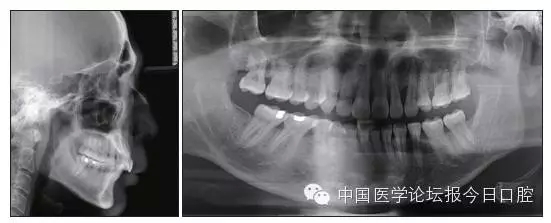

X線檢查

全口曲面體層片(圖3)顯示,患者全牙列牙槽骨吸收;根尖片(圖4)示11近中牙槽骨角形吸收已達(dá)根尖1/3,21牙槽骨嵴頂吸收至根1/2,23牙槽骨近中骨板角形吸收至根1/2。磨牙區(qū)骨嵴頂吸收3mm。治療前頭顱側(cè)位片見(jiàn)圖3,治療前ODS模型見(jiàn)圖5。

圖3 治療前頭顱側(cè)位片及曲面體層片